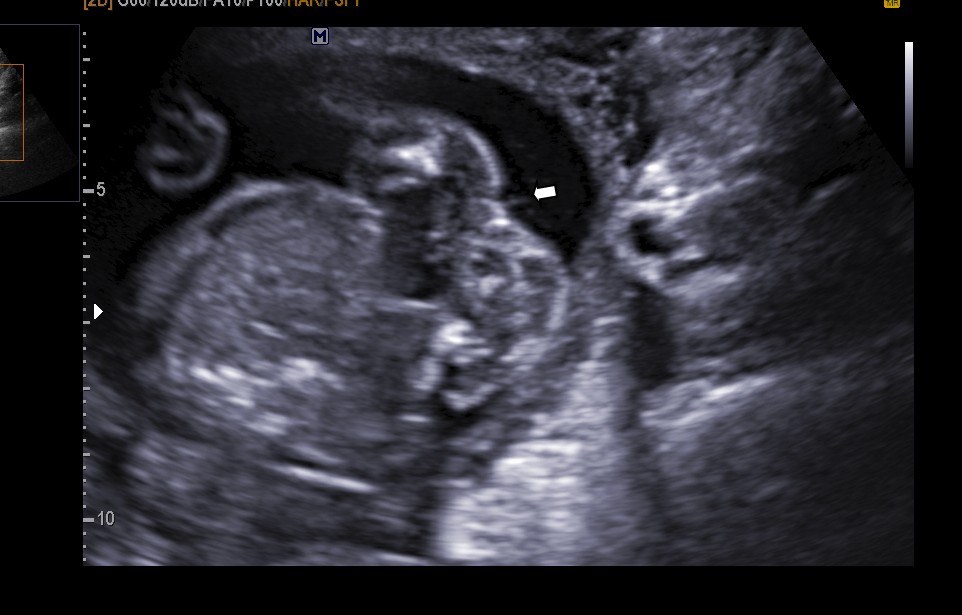

AND SHE's ALL GIRL. Tech was 100% sure and we got to see the 3 lines 5 different times. So excited. Goodluck to everyone else swaying.Attachment 921

and another one just to make sure!!Attachment 923